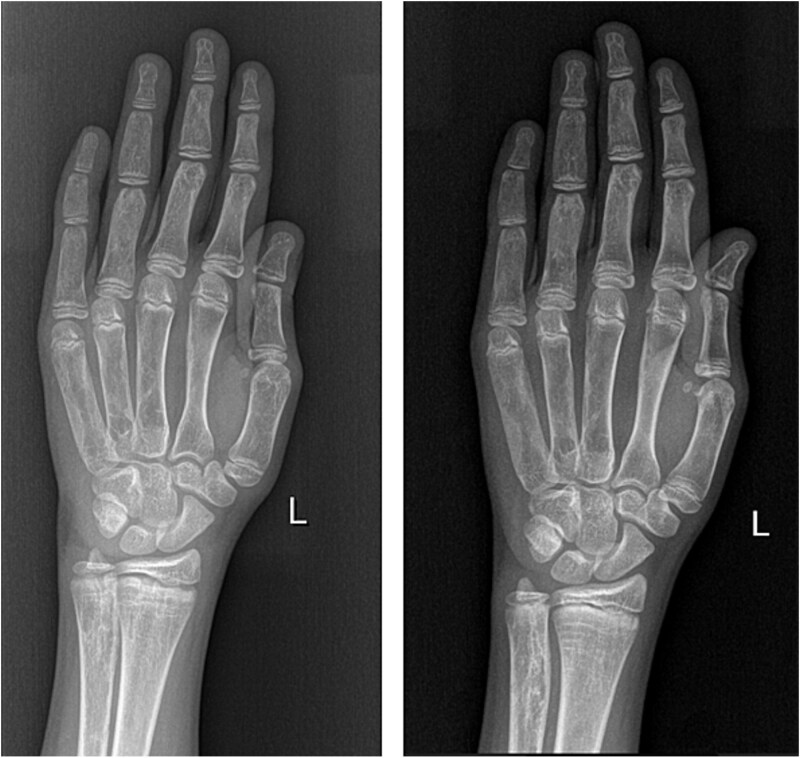

Fibrous dysplasia/McCune-Albright syndrome (FD/MAS) is a rare condition caused by a mutation in the GNAS locus. Apart from endocrinopathies, some cases are characterized by excessive fibroblast growth factor 23 (FGF23) production from abnormal fibro-osseous tissue in FD lesions, resulting in increased renal phosphate excretion. We present a girl with FD/MAS and severe skeletal burden, evidenced by the presence of polyostotic fibrous dysplasia, which was complicated with bone fractures. She also had hyperthyroidism and GnRH-independent precocious puberty. She received zoledronic acid infusions in preparation for hip surgery. Despite optimal conventional management with oral phosphate and alphacalcidol, which was poorly tolerated, she presented persistent hypophosphatemia. To control hypophosphatemia and its deleterious effects on bone health, treatment with burosumab off-label at a dose of 0.66 mg/kg (20 mg) every 2 wk was initiated. Serum phosphate levels normalized within 2 wk of treatment. Laboratory results showed improvement in serum alkaline phosphatase (ALP) and PTH levels. After the second injection of burosumab, phosphate and PTH rose above the normal range with normal vitamin D levels; therefore, the interval between doses was increased to 3 wk, and calcium 500 mg daily was added. However, phosphate levels dropped again below normal range, so she had to return to 2-weekly injections of 20 mg. After 11 mo on burosumab, she remains with high normal phosphate levels and normal PTH and ALP values. Burosumab is well tolerated, with no adverse events to date. Burosumab is a human monoclonal antibody against FGF23 that reduces the risk of developing FGF23-mediated hypophosphatemia and its associated complications. Burosumab should be considered as an effective and safe alternative strategy for FGF23-mediated hypophosphatemia in FD/MAS for those who either cannot tolerate or do not respond to conventional therapy. To our knowledge, this is the fourth published case worldwide describing successful treatment with burosumab in FD/MAS.